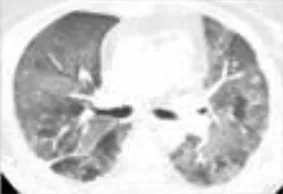

A diverse spectrum of radiographic features of pneumonitis may be found on CT imaging of the thorax. Five major subtypes have been recognized (Table 3): organizing pneumonia (OP), ground-glass opacities (GGO), nonspecific interstitial pneumonitis (NSIP) (Figure 1), hypersensitivity pneumonitis (HP), and acute interstitial pneumonia (AIP) (Figure 2) associated with the acute respiratory distress syndrome (ARDS) (Nishino et al., 2016b; Naidoo et al., 2017). The radiologic subtypes are consistent throughout the clinical course of ICI-Pneumonitis, although multiple histologic subtypes may coexist in the same patient, while evolution to other histologic subtypes over the course of ICI-Pneumonitis has been reported (Koelzer et al., 2016; Naidoo et al., 2017). Radiographic patterns of pneumonitis may correlate with clinical severity and grades of pneumonitis. AIP and ARDS correlate with more severe pneumonitis and a worse prognosis followed by OP, while NSIP and HP are associated with lower-grade pneumonitis. Thus, radiographic correlates of pneumonitis are significant prognosticators of pneumonitis outcomes and may assist in the management, follow-up, and monitoring of these patients (Nishino et al., 2016a; Nishino et al., 2017b).

| Nonspecific Interstitial Pneumonitis (NSIP) | Nonproductive cough, dyspnea typically develop over weeks to months. Bibasilar crackles | Bilateral, reticular markings, traction bronchiectasis, and ground-glass opacities typically localizes to the lower lung zones; subpleural sparing | 1–2 | ![]() |